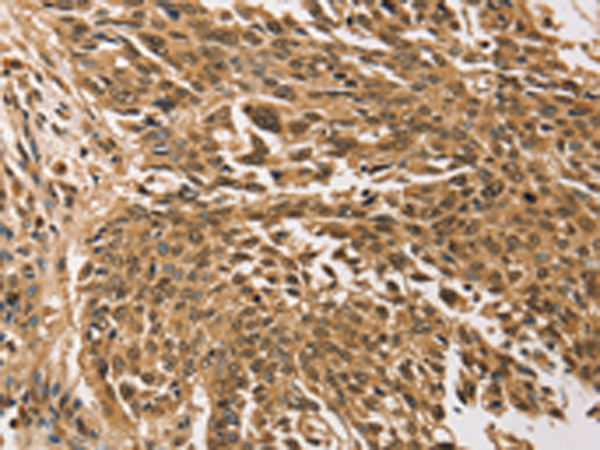

Immunohistochemical analysis of paraffin-embedded Human lung cancer tissue using #43168 at dilution 1/30.

,

Immunohistochemical analysis of paraffin-embedded Human ovarian cancer tissue using #43168 at dilution 1/30.